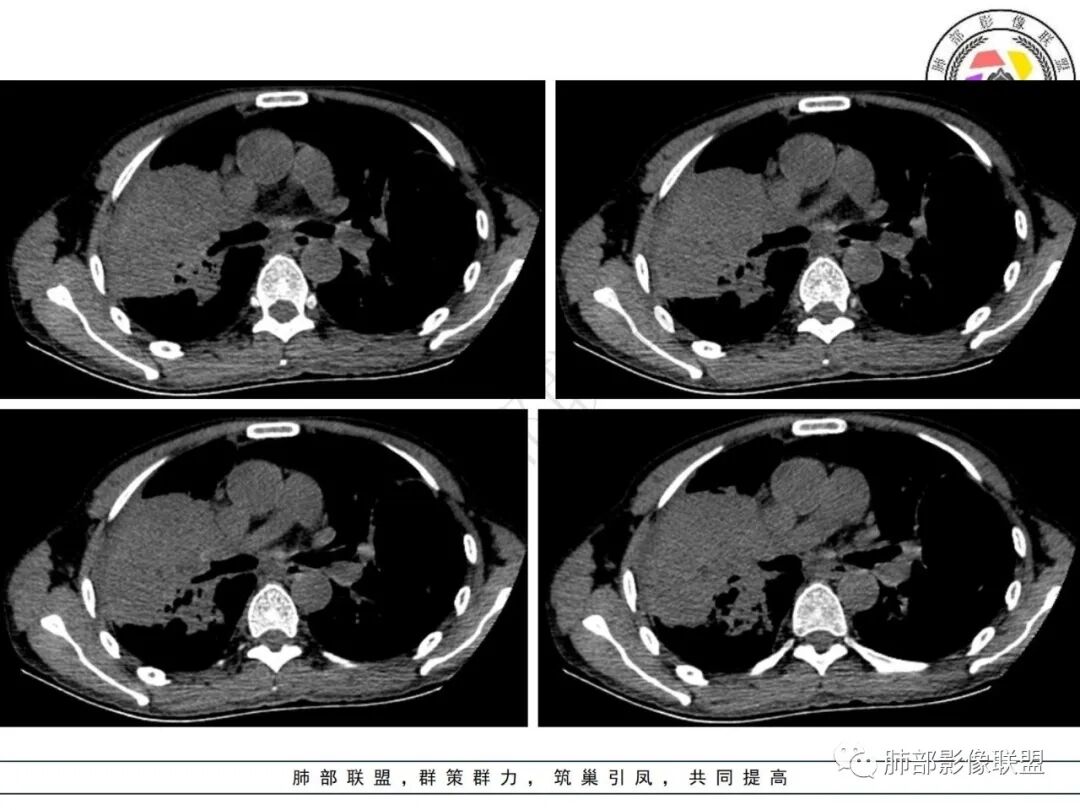

1.病例特点:中年男性,气促,中长病程。贫血明显,无发热。实验室轻度异常(C反应蛋白升高)。双肺多发结节、片状影,边界可分辨,多见支气管穿行,走形僵直。左肺上叶较大囊腔,腔内分隔明显,壁薄不均,可见结节样增厚,相邻肺组织膨胀不全。右肺上叶块影巨大,多支气管穿行,前段支气管闭塞,后段支气管扩张。余支气管管壁前段增厚。右上纵隔多发肿大淋巴结。右侧胸腔积液。

2.小结:临床病史及实验室检查与影像表现不相称,肺部块影及囊腔型病灶,应警惕新生物。右肺块影伴支气管闭塞,更多符合支气管肺癌等恶性肿瘤。

左肺囊腔性病灶,分隔,壁结节样增厚,也更符合恶性肿瘤,腺癌等为先。淋巴瘤可以,但并非常见。影像有时不宜越俎代庖,尤其是征象不够典型的,须结合病理检查。囊腔影较大时,邻肺膨胀不全应仔细甄别。